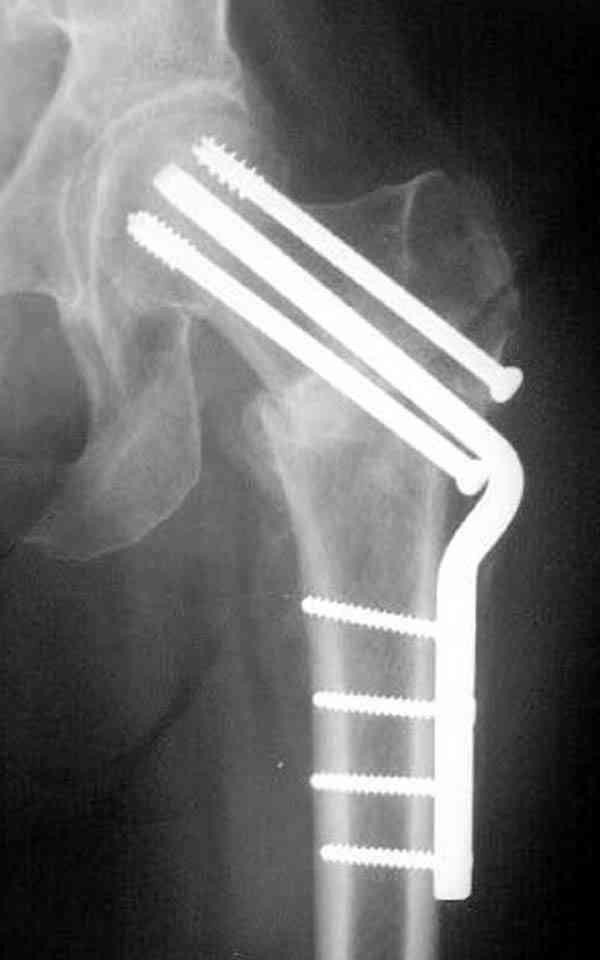

Спасибо за отклик.Хотелось бы для убедительности больше снимков, сделанных после падения, если это было, Ваших оперированных пациентов.Каюсь, но будучи в гриппозном состоянии, плохо прослушал детали Вашего доклада.Как ведут себя кость и фиксатор, если все же наступает перелом проксимального бедра, ведь перелом будет наверняка сложнее банального медиального.Я просил нашего гуру из США D.Kuldjanov прокомментировать тему,надеюсь он откликнется.В том углу зала, где я сидел,возник интерес к оценке Вашей работы экспертами страховых организаций.Ждем мнений.

Уважаемый Антон! У меня было всего три клинических наблюдения, снимки были продемонстрированы на московской конференции. Количества этих снимков хватило для подачи заявки, а затем и получения патента на изобретение. В свое время РОСПАТЕНТ потребовал подтверждения методики клиническими наблюдениями. У одной из больных действительно произошла повторная травма, и произошел подвертельный перелом на стороне армированной шейки бедренной кости (см. снимки). Это подтвердило основную идею изобретения - была сохранена и головка, и армированная шейка бедренной кости. Но тут не обошлось безпроблем. Анестезиологи отказались давать наркоз, а провести остеосинтез под м/а пластиной и винтом DHS не согласилась больная. Дальнейшее лечение скелетным вытяжением. На контр. Рентгенограмме через 2 месяца признаки формирования костной мозоли. Повторных обращений двух других пациентов не было. Для более детальных исследований и выводов необходимо значительно большее количество клинических наблюдений. Такие исследования могли быть проведены в условиях клиник медуниверситета. Напомню, я работаю в травмотделении провинциальной городской больницы. Насчет экспертов страховых компаний, так пусть они выскажут свое мнение. Армирование кости - это плановые операции по желанию больного, какие здесь могут быть противоречия? На армирование все больные, к моему удивлению, согласились довольно легко и сразу, поэтому остеосинтез и армирование были проведены в течение одной операции. С уважением А.М.